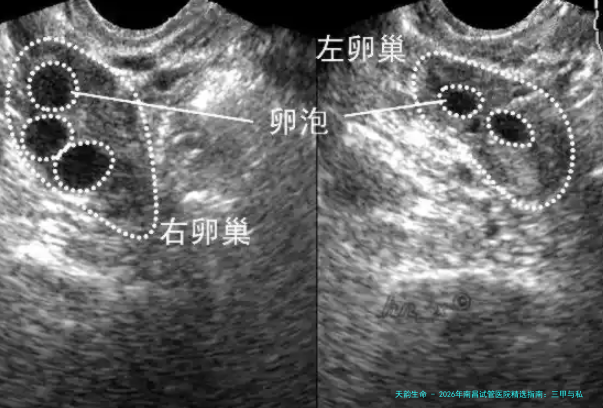

| 阴道B超监测排卵 | 1000 | 600 | 800 | 700-900 |